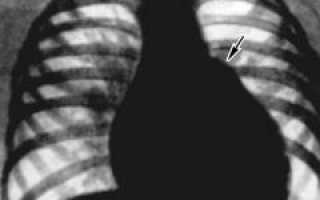

Рентгенография показывает:

- увеличение правых отделов сердца;

- застой крови в легких, проявляющийся в расширении крупных артерий;

- сужение мелких сосудов, не видимых на снимке.

Рентгенография – метод, основанный на неравномерном прохождении рентгеновских лучей через тело. На снимке видны тени и контуры органов. При дефекте межпредсердной перегородки выделяются тени расширенных легочных вен и артерий из-за застоя крови, объем которой может превышать норму в три раза. Особенно заметно увеличение легочной артерии.

Рентгенография выявляет:

- увеличение правой части сердца;

- четко видимые легочные артерии, переполненные кровью из-за повышенного давления в легочных сосудах;

- увеличение легочной артерии при уменьшении аорты, что связано с изменением давления в этих сосудах.